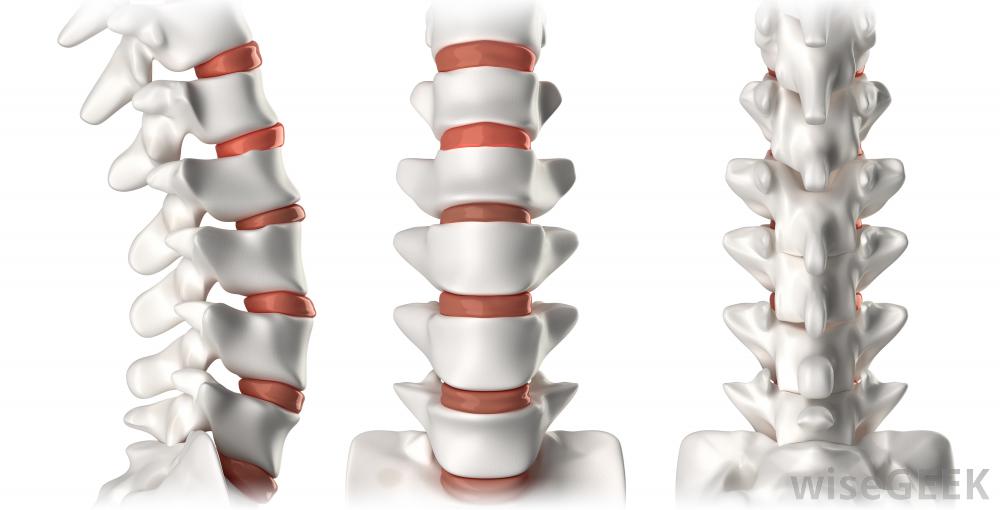

颈椎融合术结合了植骨和器械,使脊柱上部更加稳定脊柱后凸,或脊柱前屈,颈部疼痛,或椎间盘摘除部位周围出现新的椎间盘和压迫问题。医生有时建议再次手术以再次尝试融合,这可能是仅有的一次融合不伴随椎间盘切除术的情况。或者,建议手术治疗颈椎的新问题,例如压迫的神经或新的椎间盘。颈椎融合术后活动范围的丧失取决于融合的脊柱节段的数目。单一节段不太可能导致明显的损伤,但多层次融合可能会影响人们的转头能力。这是可以理解的,因为允许活动的弹性椎间盘已被骨取代。物理疗法通常可以帮助人们弥补这些损失,但这需要时间尽管有可能的缺点,神经外科医生和骨科医生定期进行颈椎融合术,他们的病人往往报告积极的结果,大多数需要这种手术的人是在极端和无情的疼痛对于许多病人来说,放弃少量的颈部功能来达到缓解似乎是一种公平的权衡,当由称职的外科医生进行这项手术时,人们也被吸引到与此相关的高恢复率。